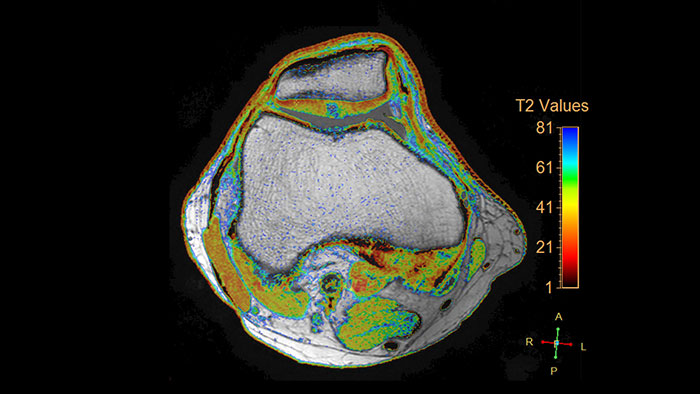

Visualize cartilage structures

Enables the visualization of cartilage structures integrated with color-coded T2 maps. Positioning of cartilage-shaped, layered region of interest is used to assess variation of T2 values across the cartilage depth to determine the degradation of the cartilage.